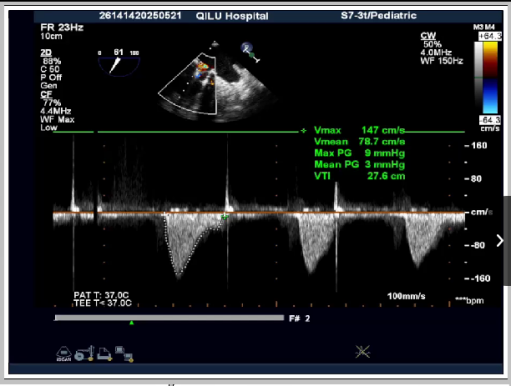

第一次高压球囊扩后超声:平均压差:3mmHg 峰值压差:9mmHg

第二次高压球囊扩后超声:平均压差:2mmHg 峰值压差:6mmHg

本次手术患者为二尖瓣生物瓣置换术后,重度反流。治疗团队术前对CT报告进行仔细评估,选择更大尺寸的瓣膜型号,术中通过经心尖入路,多学科团队密切配合,完成瓣膜精准释放,再用Atlas Gold球囊高压后扩,将25#原人工Mosaic生物瓣环扩断。患者术中生命体征平稳。术后超声显示人工瓣膜功能恢复理想,瓣膜无中心及瓣周反流,二尖瓣跨瓣压差仅为2mmHg,效果非常满意。